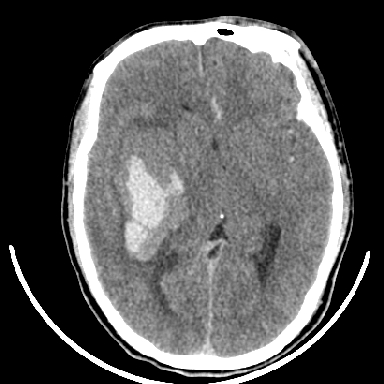

标题: CT6056:脑出血(血管畸形?)

m 40突发头痛左侧偏瘫3小时

考虑高血压性脑出血,依据:

1是高血压性脑出血的好发部位,形态呈肾形,是高血压性脑出血的常见形状

2增强时占位效应加重了,考虑出血还没有停止

3病灶周围水肿不是太厉害,一般肿瘤出血水肿多非常明显

4病灶周围的‘软组织’影没有明显的强化

5至于脑血管畸形引起的出血,暂时没有看到明显的畸形血管影,也不太支持

支持右侧基底节脑出血

右侧基底节区脑出血.

支持右侧基底节区(主要为外囊区)原发性脑出血。

但脑出血早期做增强是不是有点太冒险了?

另附部分资料:“血液溢出血管外形成血肿,其内含有大量血红蛋白、血浆白蛋白,球蛋白,因这些蛋白对x线的吸收系数高于脑质,故ct呈现高密度阴影,ct值达40~90h,最初高密度灶呈非均匀一致性,中心密度更高,新鲜出血灶边缘不清。基底节区血肿多为“肾”型,内侧凹陷,外侧膨隆,因外侧裂阻力较小,故向外凸,其它部位血肿多呈尖圆形或不规则形”

术中抽出40ml陈旧血液,血肿底部似见一条索血管影